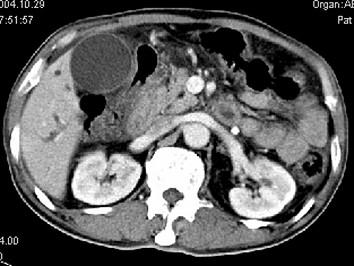

问题 男,58岁,患者右季肋区疼痛,皮肤黄染,可触及肿大胆囊,B超提示胆囊颈部肿块影,CT所见如图,最可能的诊断是 ( )

选项 A、慢性胆囊炎 B、胆囊腺肌增生症 C、胆囊癌 D、胆囊黄色肉芽肿 E、胆囊息肉

答案 C